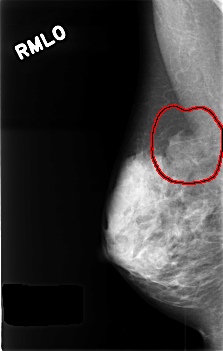

FILE: C_0430_1.RIGHT_MLO.OVERLAY

TOTAL_ABNORMALITIES 1

ABNORMALITY 1

LESION_TYPE MASS SHAPE ASYMMETRIC_BREAST_TISSUE MARGINS ILL_DEFINED

ASSESSMENT 3

SUBTLETY 4

PATHOLOGY BENIGN_WITHOUT_CALLBACK

TOTAL_OUTLINES 1

BOUNDARY